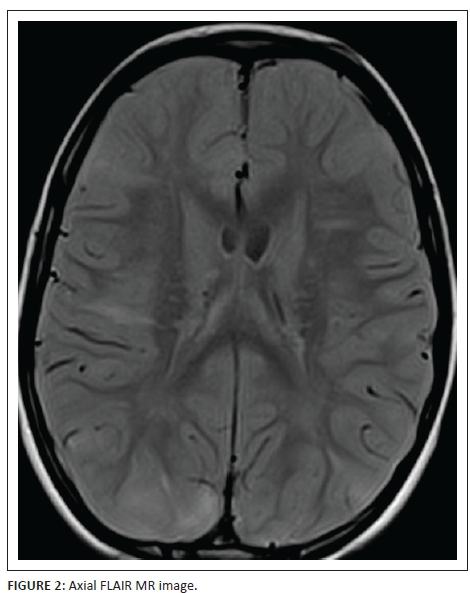

Figure 2 is an axial FLAIR sequence image demonstrating numerous transmantle radial migration lines as hyperintense bands. These lines traverse the white matter from the ventricular ependymal surface to the subcortical white matter. One such band in the right frontal lobe is associated with a cortical-subcortical tuber as are two further bands in the postero-inferior parietal lobes on both sides.